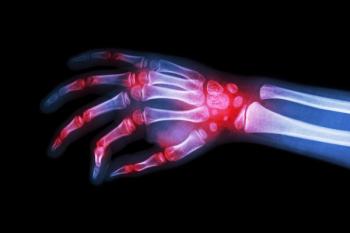

The risk for incident autoimmune inflammatory rheumatic disease (AIRD) was greater among patients with a history of COVID-19 infection.

A cross-sectional study finds that patients with rheumatoid arthritis receiving disease-modifying antirheumatic drugs (DMARDs) exhibit a reduced immune response to the COVID-19 vaccine compared with controls.

An observational registry study revealed that inflammatory disease activity is not the only factor influencing the achievement of treatment targets for patients with rheumatoid arthritis (RA).

New data presented at ACR 2023 highlighted the differences in rates of flares and Boolean 2.0 remission rates compared to patients with rheumatoid arthritis who continued a tumor necrosis factor inhibitor (TNFi).

A nationwide cohort study linked biologic disease-modifying antirheumatic drugs with decreased risks for the onset of autoimmune thyroid disease in patients with rheumatoid arthritis.

A network meta-analysis confirmed the efficacy of methotrexate for patients with rheumatoid arthritis (RA) and validated it as the primary reference conventional synthetic disease-modifying antirheumatic drug for treatment in this population.